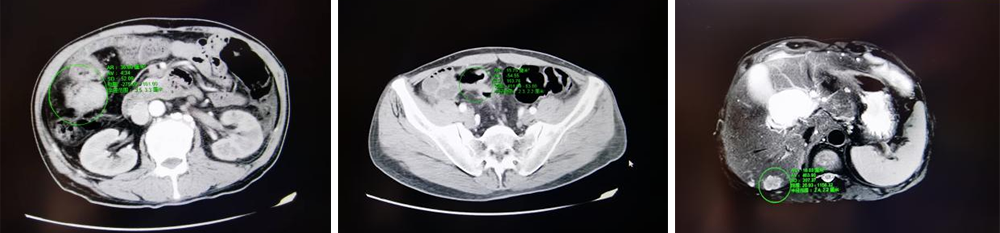

4周期规范治疗后,患者下腹疼痛、排便异常等症状显著缓解,复查增强CT显示原发灶及转移灶均明显缩小,疗效评估为病情稳定,不仅有效延缓了疾病进展,更改善了患者全身状态,为后续急症处置和根治手术奠定了关键基础。

经多学科团队联合评估并完成充分术前准备后,2026年1月12日,结直肠胃腹部肿瘤外二科团队为患者实施腹腔镜下乙状结肠切除术+右半结肠切除术+肝部分切除术,同步切除结直肠两处病灶及肝脏转移灶。

此次手术为腹腔镜下多脏器精细操作,对团队技术和协作能力要求极高。术中,团队成员默契配合、精准操作,在彻底清除病灶的同时最大限度保留正常脏器功能,手术全程出血少、创伤小。1月19日,患者各项指标恢复良好,顺利康复出院。术后病理结果显示,患者病灶被完整切除,肠周淋巴结未见癌转移,肝转移灶内大量坏死,证实前期化疗与手术的联合治疗方案取得显著疗效。